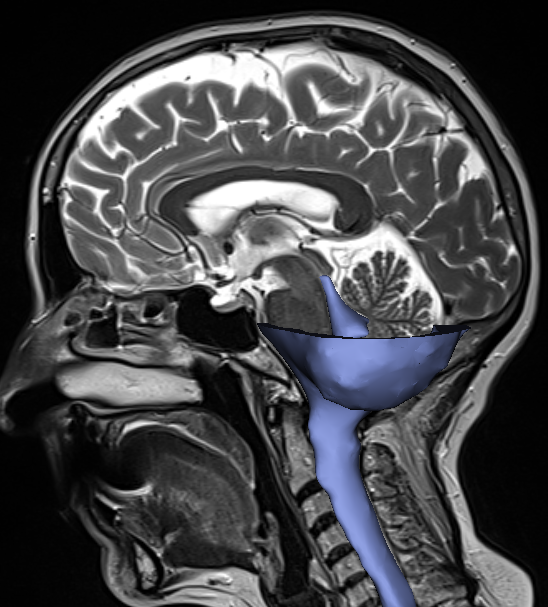

Computational fluid dynamics (CFD) is a numerical technique that allows us to calculate the flow within a predefined volume. For the CSF, this three-dimensional volume is extracted from magnetic resonance images (MRI) of the head, as shown in Figure 2. The natural flow of CSF is affected by several internal and external factors with an important role of other cerebral fluid systems including the cardiovascular and the lymphatic system. For instance, biological mechanisms such as CSF production and absorption and pulsations of the arteries supplying the brain change the fluid dynamics. Hence, to capture the flow in a realistic way, it is necessary to incorporate those mechanisms. The resulting CFD models allow us to investigate in detail what happens in a healthy person and what goes wrong or changes in persons with neurological abnormalities.